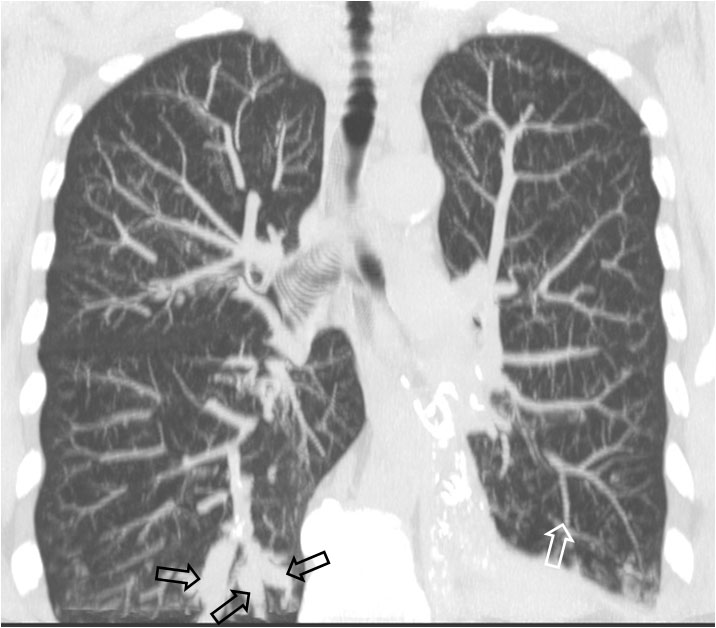

SIGNO DE LAS VÍAS DEL TRANVÍAVIAS2Se trata de otro signo de bronquiectasias. La presencia de imágenes paralelas o ligeramente convergentes, situadas con más frecuencia en los lóbulos inferiores, dirigidas hacia el hilio, corresponde a bronquiectasias tubulares. Las vías corresponden a las paredes engrosadas de los bronquios dilatados (flechas).

Hay que recordar que también existe un Signo de las vías del tranvía en el TEP (el contraste alrededor del trombo), así como en el meningioma del nervio óptico (el realce de la vaina) y en el Síndrome de Sturge-Weber (las calcificaciones corticales).